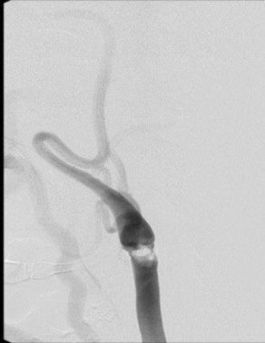

Karotis hastalığında cerrahi tedavi (Karotis endarterektomi)

Boyuna karotis damar üzerindeki cildin 5cm'lik kısmına lokal anestezi uygulanır. Daha sonra 4-5cm'lil kesiden damara ulaşılır. Damar duvarı açılır ve damar içerisindeki plak çıkartılarak damar direk veya yama konularak kapatılır. Ortalama operasyon süresi 1.5-2 saat civarındadır.

Operasyon sonrası hasta 2-3 gün takip edildikten sonra taburcu edilir.

Resim 1,2. Karotis endarterektomi (Karotis damar içerisinden plak çıkarımı)

Operasyon sonrası çok nadir olarak kanama (%0,5-1), inme, boyunda hematom (pıhtı birikimi) gibi komplikasyonlar nadir olarak gelişebilmektedir.

Cerrahi operasyon ile inme riski %2’ye kadar düşürülmektedir.